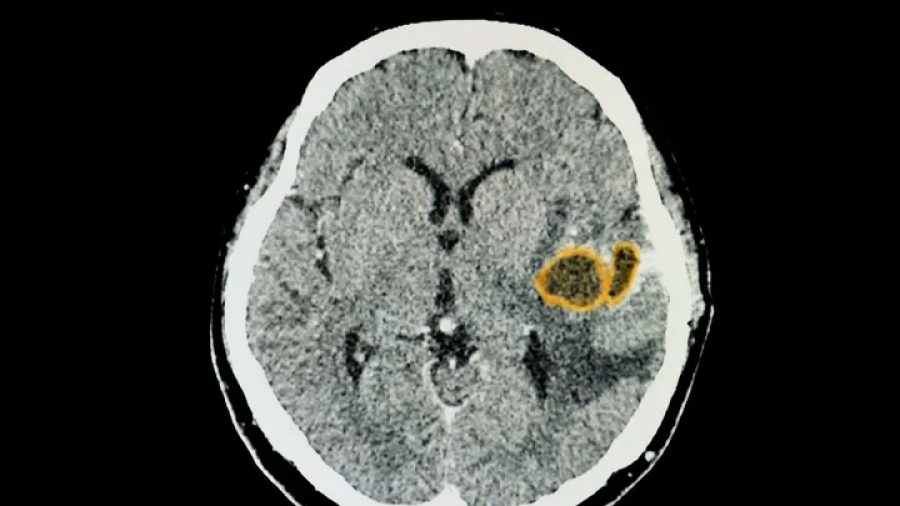

Οι περιπτώσεις εγκεφαλικών αποστημάτων σε παιδιά τριπλασιάστηκαν πέρυσι στη νότια Νεβάδα, θέτοντας σε συναγερμό τα Κέντρα Ελέγχου και Πρόληψης Νοσημάτων (CDC) των ΗΠΑ τα οποία ξεκίνησαν να διερευνούν πιθανούς λόγους για την εν λόγω απότομη αύξηση.

Τα εγκεφαλικά αποστήματα συνήθως διαγιγνώσκονται με μαγνητικές τομογραφίες, εξετάσεις αίματος ή/και εξετάσεις δειγμάτων από τη μολυσμένη περιοχή.

Το απόστημα στον εγκέφαλο ενός – κατά τα άλλα υγιούς – ατόμου συνήθως προκαλείται από βακτηριακή λοίμωξη. Τα μυκητιασικά εγκεφαλικά αποστήματα τείνουν να εκδηλώνονται σε άτομα με εξασθενημένο ανοσοποιητικό σύστημα. Η λοίμωξη προκαλεί τη διόγκωση του εγκεφάλου από τη συλλογή πύου και νεκρών κυττάρων.

Ένα εγκεφαλικό απόστημα σχηματίζεται όταν μύκητες, ιοί ή βακτήρια φτάνουν στον εγκέφαλο μέσω μιας πληγής στο κεφάλι ή μιας λοίμωξης σε κάποιο άλλο μέρος του σώματος.